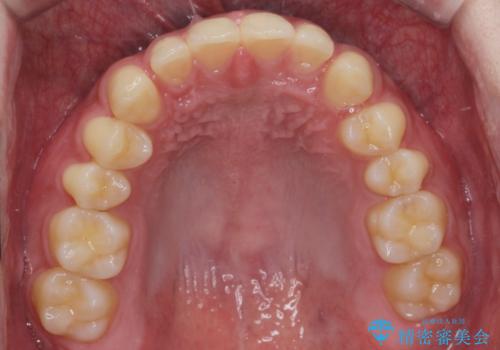

ナイトガードで歯の予防をしたい。

- 歯軋りが気になるとの事で来院。

歯が割れたりするのを予防したいとの事でしたのでナイトガードを作製しました。

ナイトガードを使用することにより歯が割れるリスクが低くなります。